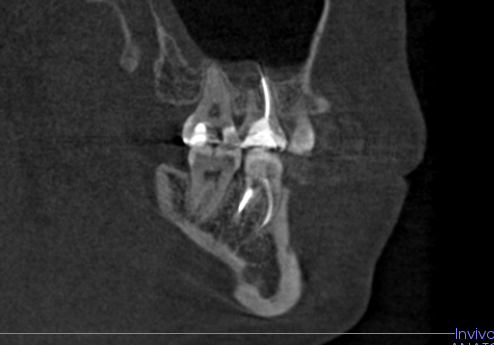

Врач второй клинике увидела на снимке 4 канала, и сказала, что первым врачом, лечившим зуб, были вылечены только 2. Также что вверху зуба инородное тело, его необходимо вытаскивать, лечение будет проходить в 2 приема. Нужно ходить с лекарством в зубе месяц и пытаться извлечь лишний материал от первого лечения через зуб, а в случае если не получится его оттуда вынуть через зуб, то пропихнуть его в пазуху и оно должно само через пазуху. Корни зуба находятся в этой пазухе.

Обратились еще в одну клинику, там врач сказал, что материал заложен неправильно, с пробелами, и выходит за пределы корня зуба. Зубных каналов пролечено 2, причем 3 она видит, а 4й нет. Также есть 2 варианта лечения: попробовать достать этот материал через зуб и проходить с лекарством 2 недели-месяц.

Либо если не получится достать материал на первом приеме, выход только пломбировать полностью зуб как есть и оставлять этот материал, и уже прорезать десну снаружи и доставать через десну.

Ниже прикреплю скриншоты 3Д снимка с проблемным зубом, если кому-то потребуется полностью 3Д снимок напишите почту или другие контакты, я пришлю полную версию снимка.